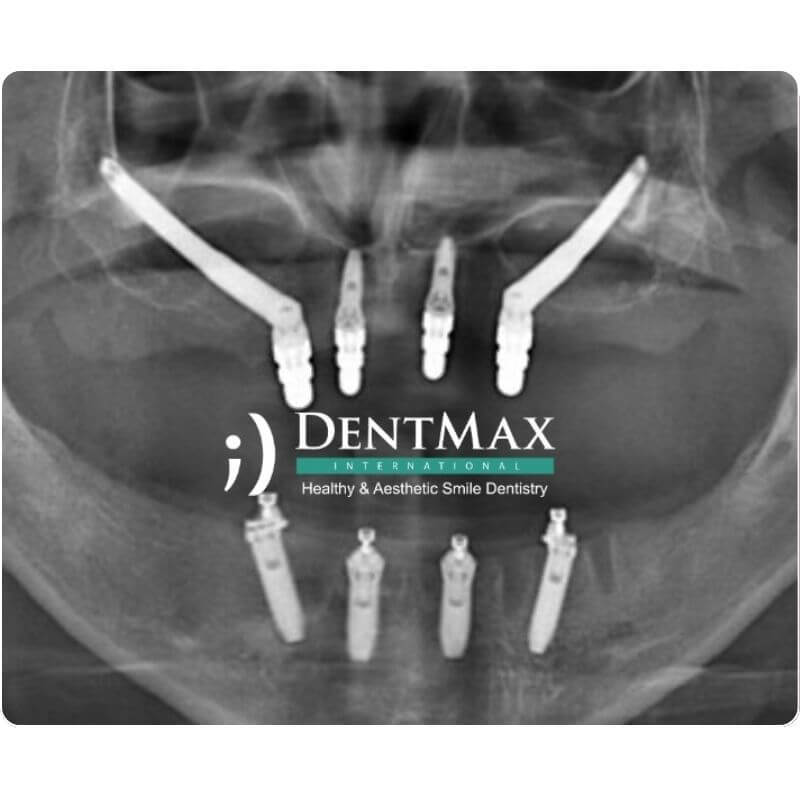

Phase I - Surgical Stage